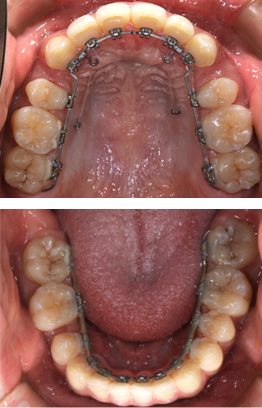

見えない矯正装置(舌側矯正)

当院では、見えない矯正(舌側矯正)を主に行なっております。メリットは矯正装置を歯の裏側に装着することで外から目に触れないということです。

またスポーツをする上でも口周辺にコンタクトがあった場合に口腔内の粘膜に外傷を負うリスクが減る利点があります。